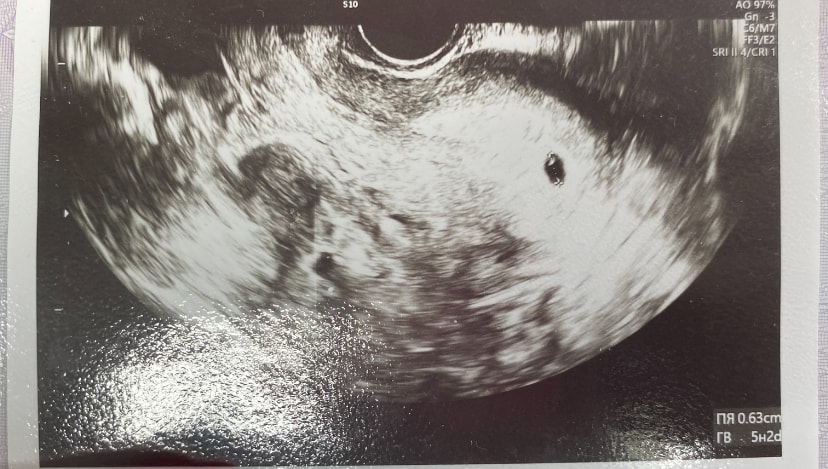

Я не специалист по узи, но 2 точки вижу

Одно пя у вас,маточная беременность крепится в функциональный слой эндометрия,на фото вот эндометрий,светлый и в нем пя,а те включения за пределами эндометрия и это не пя уже

Вторая точка не в матке же вроде

И если присмотреться там еще 4 включения рядом

На снимке точно одно пя

Кристина, может вы услышали что хотели услышать?) у вас точки про которые вы говорите не в матке даже и к плодному яйцу не имеют никакого отношения. Беременность одноплодная